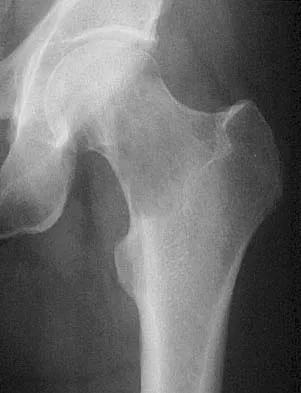

Question 47High Yield

A 53-year-old patient is seen in the emergency department after sustaining a fall onto her left hip. A current radiograph is shown in Figure 40. What is the best treatment option?

Explanation